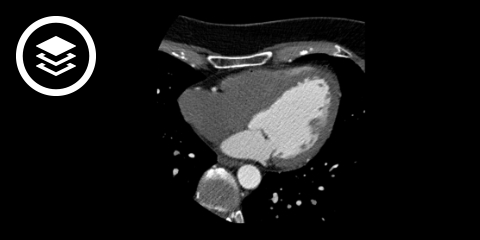

CT-Fallbeispiel

DICOM-Modelle können auf Mobilgeräten leider nicht angezeigt werden.

- Bildquelle DICOM-Viewer: Datensatz freundlicherweise zur Verfügung gestellt durch die Klinik für diagnostische und interventionelle Radiologie, St. Vinzenz Hospital Köln